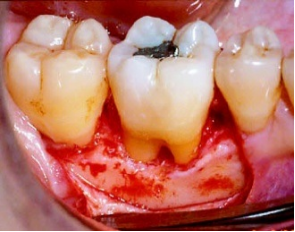

手术治疗

对于一些仅采用基础治疗后效果不佳的牙周炎,可以通过适当的手术治疗挽救患牙,包括牙周翻瓣术、牙龈切除术等。

![图片[14] | 健康生活 从“齿”出发 !预防牙周炎,远离“老掉牙”~ | 星尘资源网](/wp-content/uploads/2025/10/1759749596482_13.png)